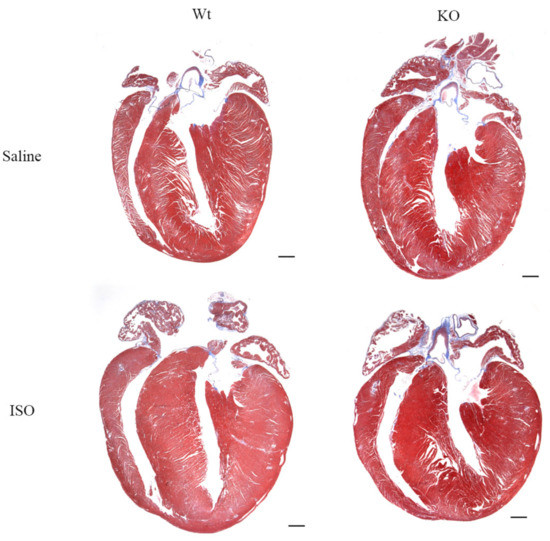

3.5. Impact of Isoproterenol Induced Stress on SLMAP3-KO Hearts